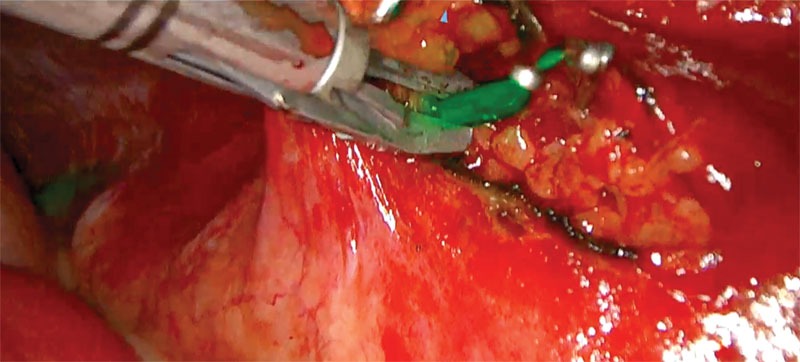

Surgical outcome for chylothorax in small animal patients is highly variable, with the prognosis more guarded in cats than in dogs.1,13 Traditional surgical interventions for idiopathic chylothorax are highly invasive, typically requiring open chest surgery (Figures 1 and 2) with the possibility of added abdominal laparotomy.3,4 Owners may be averse to such highly invasive procedures, with a possibility of nonresolution or continued need for pleural effusion evacuation. The use of minimally invasive surgery in small animals has made advances in the last several decades, and its use has been applied for surgical conditions, such as chylothorax.13-15

Figure 2. Subtotal pericardiectomy in a cat via median sternotomy. Also shown is the transthoracic omentalization. Photo courtesy Dr. Eric Monnet